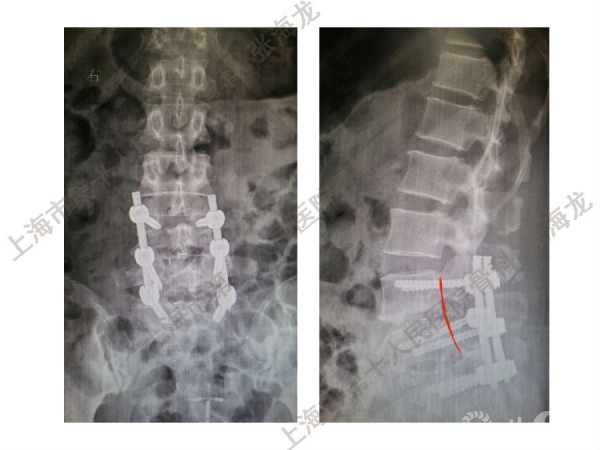

2008年3月至2010年8月,上海市第十人民医院骨科随访49例腰椎滑脱症(峡部裂型和退变型)患者,对比23例微创手术MIS-TLIF和26例开放手术治疗腰椎滑脱症的临床及影像学结果,进行了回顾性研究。

研究发现,Wiltse入路Mis-TLIF更直接的暴露峡部及关节突,对脊柱稳定性的影响较小;彻底松解辅助双重提拉复位Mis-TLIF,对于峡部裂型滑脱有较好的复位效果;对于峡部裂型滑脱,提拉复位在影像学参数上有一定优势;与原位融合相比,ODI.VAS.JOA无明显差异(样本量有限);对于退变性滑脱,单纯撑开椎间隙与原位融合可以获得较好疗效。